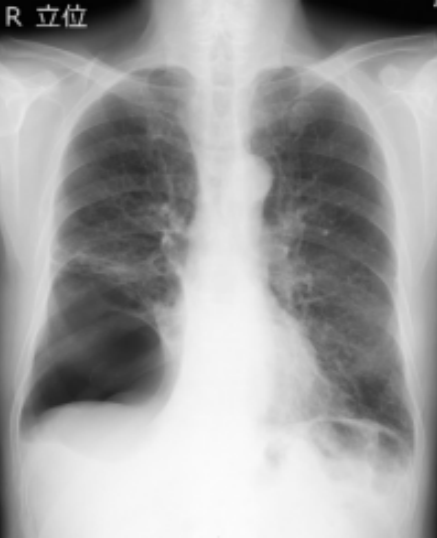

和自发性气胸病史,日常活动并没有受限制。术前呼吸功能检查显示轻度阻塞性障碍。术前胸片显示一个肺大泡泡占据了右侧胸腔下半部分(图1)。

图1. 胸片显示一个肺大泡泡占据了右侧胸腔下半部分